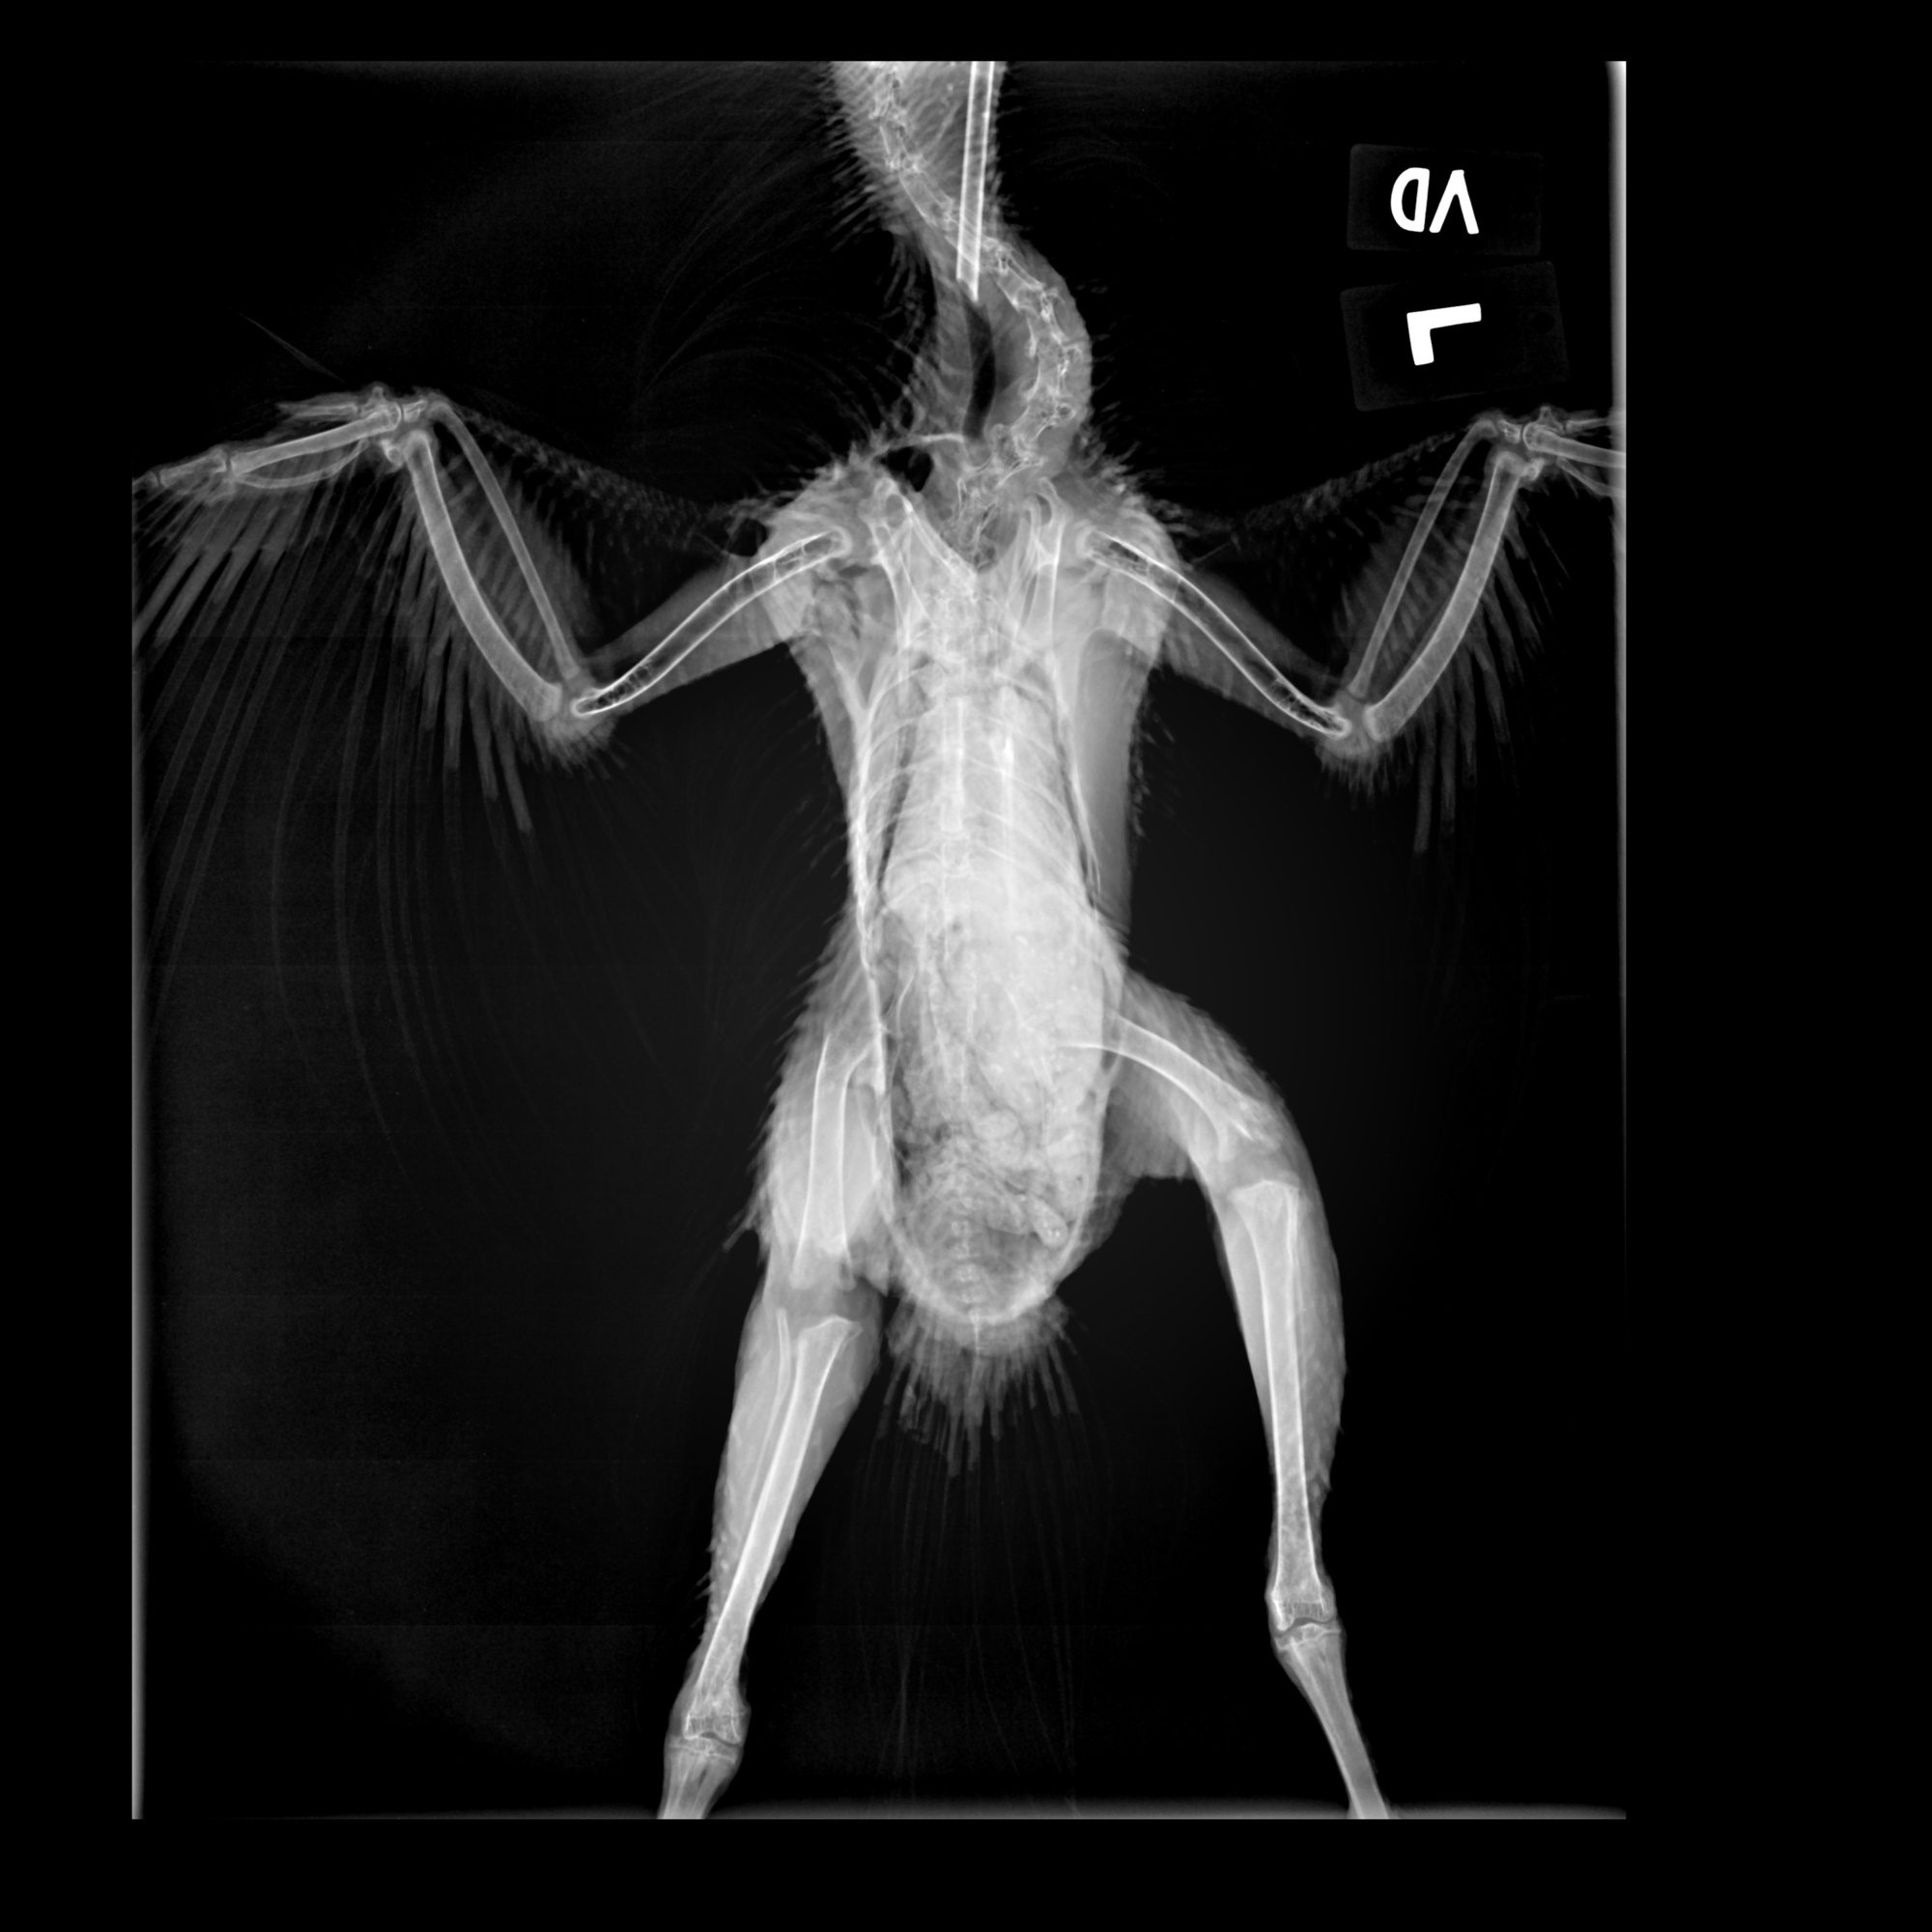

here is a Xray of my bird..really wonder if it's not just orthopedic..The space in his knees are huge. Can I give some citracal +D3?